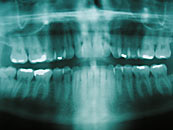

Parodontitis

Die Parodontitis ist eine entzündliche Erkrankung des Zahnhalteapparates. Sie wird durch eine Ansammlung von Bakterien (Zahnbelag und Zahnstein) entlang der Ränder des Zahnfleischs (Gingiva) verursacht. Wenn diese Ablagerungen nicht beseitigt werden, tritt eine Entzündung auf. Es bilden sich am Zahnrand Taschen, in denen sich die Bakterien unter für sie optimalen Bedingungen vermehren können. Das Zahnfleisch schwillt an, ist gerötet und es kommt zu Blutungen. Im weiteren Verlauf wird durch die tiefer werdenden Taschen und einer stärker werdenden Entzündung der Knochen abgebaut. Es kommt zu einer Lockerung und das Risiko besteht, dass der Zahn ausfällt.

Funktionsstörungen im Kausystem, Störungen im allgemeinen Stoffwechsel, Stress, Alkohol- sowie Nikotinmissbrauch und mechanische Traumen können den Krankheitsverlauf negativ beeinflussen.

Es wird angenommen, dass zwischen 60 und 70% aller Zahnverluste durch eine Parodontitis verursacht werden. Aber diese Erkrankung führt nicht nur zu Zahnverlust, sondern scheint auch andere weitreichende Folgen zu haben.

Neuere Forschungsergebnisse zeigen, dass durch eine chronische Parodontitis das Risiko für Schlaganfälle, koronare Herzerkrankungen und Diabetes mellitus erhöht wird. Auch bei Frühgeburten konnten Zusammenhänge mit Parodontitis festgestellt werden. Somit kommt der rechtzeitigen Behandlung von Zahnbetterkrankungen eine wichtige prophylaktische Rolle zu.